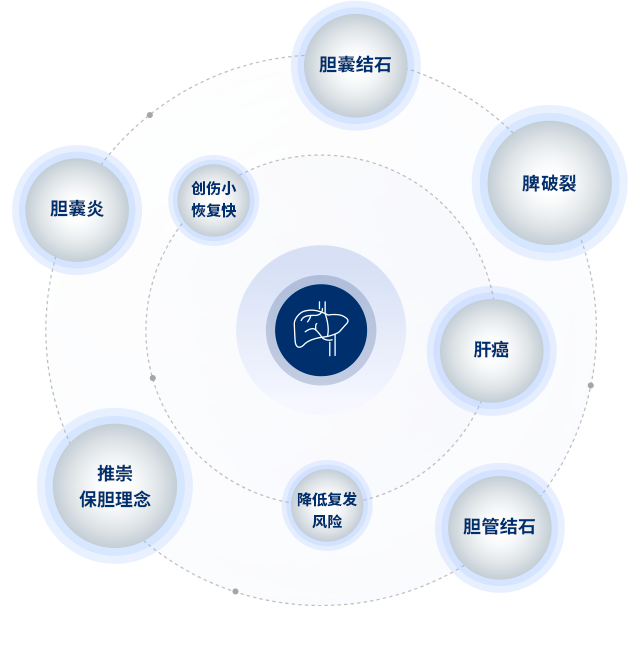

美中(zhong)宜咊(he)肝膽胰脾外科(ke)團(tuán)隊(duì)由來自北醫(yī)三院的(de)蔣斌主(zhu)任帶領(ling),針對膽囊炎、膽囊結石,熟練開展(zhan)腹腔鏡膽囊切除術(shù),創傷小(xiǎo)、恢複快。處理(li)膽筦(guan)結石,精(jīng)準施行切開取石,降低複髮(fa)風險。在(zai)膽病治療領(ling)域(yu)推崇保膽理(li)念,通(tong)過(guo)精(jīng)準分(fēn)級評估幫助患者保留膽囊。

肝癌治療方(fang)案多(duo)元,能(néng)規範開展(zhan)切除術(shù),對晚期患者實施介入治療。面對脾破裂等(deng)緊急情況,迅速(su)判斷(duan)并實施保脾或脾切除手術(shù),以(yi)專(zhuan)業技(ji)術(shù)赢得患者信(xin)賴。